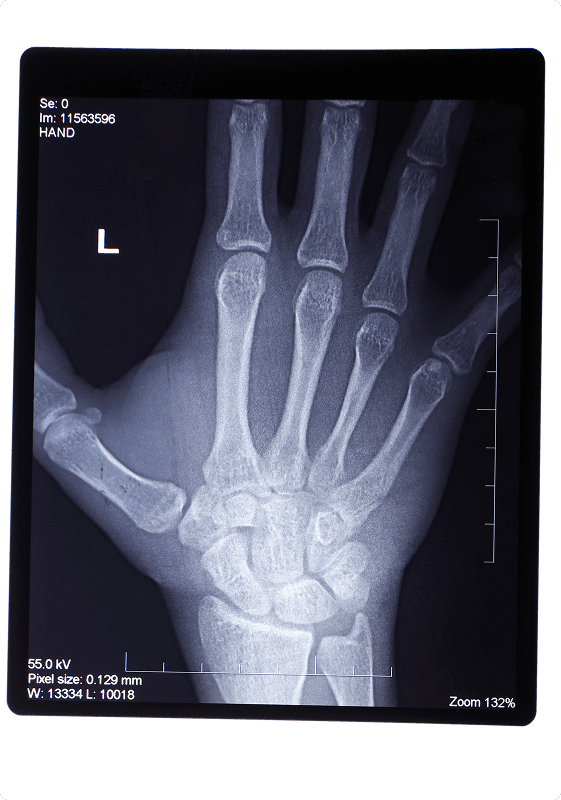

Initial evaluation includes a medical history, physical examination, and x-rays of the thumb and hand. Arthritis at the base of the thumb commonly also is associated with carpal tunnel syndrome and this may be evaluated.